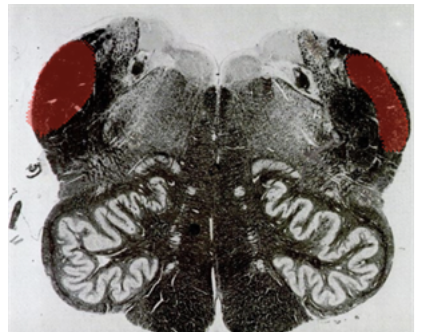

What cut of the brain stem is this?

What is this missing, which should give you a hint where it is?